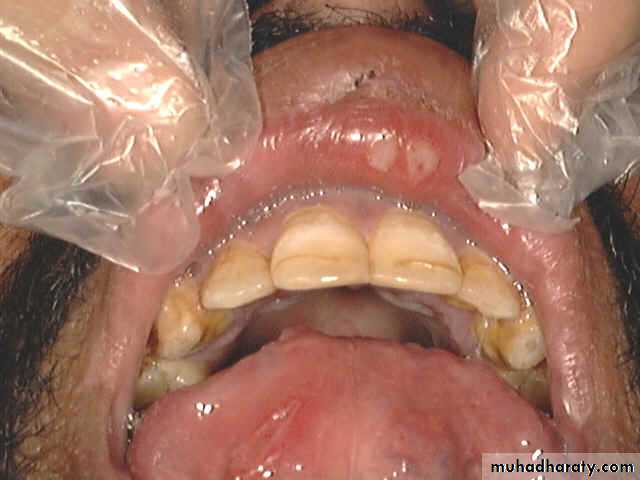

Aphthus ulcer

1- Aphthus

Recurrent ulceration of the oral mucosa of unknown aetiology. Viral, psychogenic, endocrinal and autoimmune factors have been suggested. Sometimes aphthus is due to deficiency of iron, folate or B12. Persistent aphthus ulceration especially in young males, must bring to mind the possibility of AIDS.

It's started as a small vesicle, which soon ulcerates leaving an ulcer which varies in size. This ulcer is typically quite sensitive and painful. It has a central necrotic base with a surrounding red circumference and it disappears after a few days.

Aphthus ulcers are of two types.

The minor form, which is more common, the ulcers are multiple and 3-6 mm in size. They heal within 7-10 days with no scars.

The major form, ulcers are 1-2 cm in size, less common, long lasting and heal with a scar.